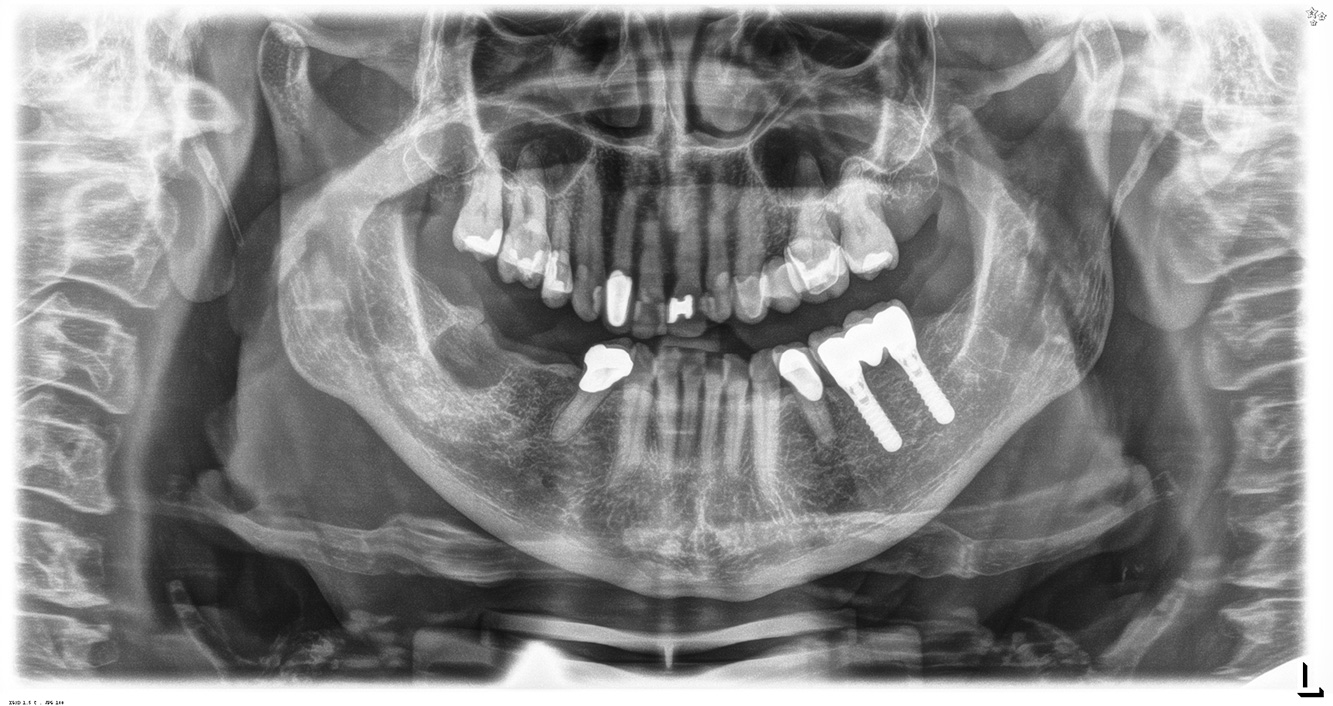

Die 68-jährige Patientin hat keine zahnmedizinisch relevanten allgemeingesundheitlichen Vorerkrankungen oder Medikation, auch aus dem Lebensstil ergibt sich kein besonderes Risiko. Die Patientin hat zwei Implantate (3. Quadrant, seit fünf Jahren) sowie eine parodontale Vorerkrankung (Parodontitis Stadium IV, Grad B) mit Zahnverlust. Derzeit zeigen sich stabile parodontale Verhältnisse, jedoch erhöht Parodontitis maßgeblich die biologischen Komplikationen bei Implantationen und es droht der Implantatverlust (21).